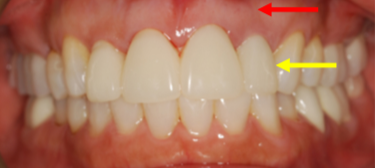

Precision Implant Placement always begins with meticulous planning using CBCT scans and dedicated implant‐planning software (Figs. 1-3). First, we virtually “insert” the implant on the CT scan so it centers beneath the future crown (Fig. 1). Then we design and fabricate a surgical guide (Fig. 2) to transfer that plan directly to the patient’s mouth. Finally, the guide seats on the patient’s teeth during surgery to ensure exact implant placement (Fig. 3), achieving both optimal bone support and prosthetic alignment.

Fig. 2: Design of the Custom Surgical Guide from the Virtual Plan